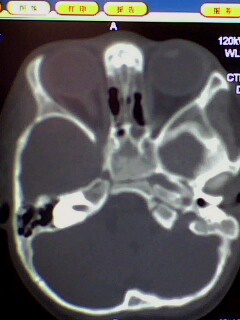

标题: PED3023:鼻咽增殖体肥大。

男,3岁小儿,经常睡觉时张口呼吸、打鼾。

1、鼻咽增殖体肥大继发左侧乳窦炎?

2、双侧上颌窦炎?

1、左侧乳窦气房硬化型改变,是发育不完全还是鼻咽增殖体肥大阻塞咽鼓管开口引起中耳炎?

2、双上颌窦应该有炎症了吧,听好多人说,小孩副鼻窦还没发育完全也可有这种表现,究竟两者怎样鉴别?请各位战友指点。多谢